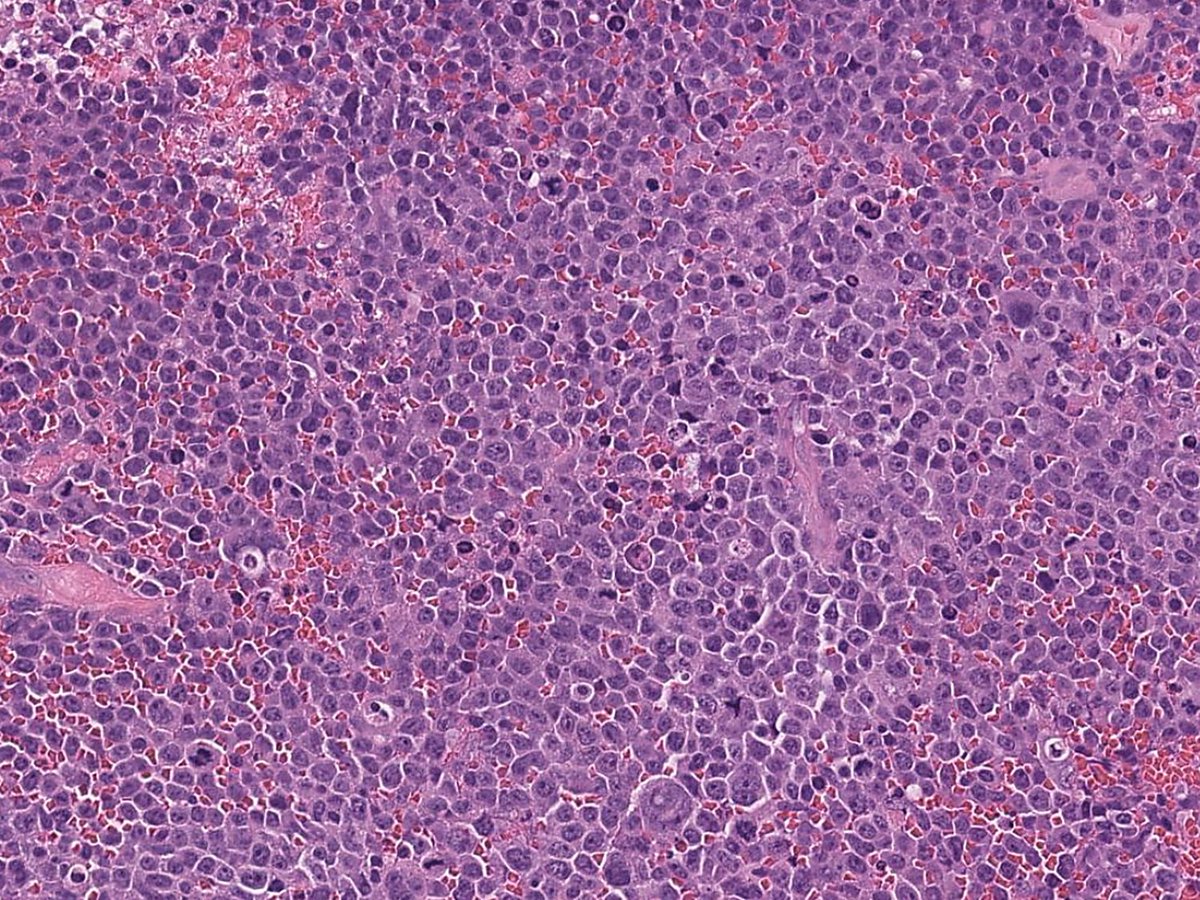

Example of a case of "Diffuse large B-cell lymphoma associated with chronic inflammation", developing in the pleural cavity of a patient with longstanding pyothorax➡️ #Hemepath #PathX #Pathtwitter #MedX #MedTwitter #Surgpath #SoMe

🩸This entity is strongly associated with EBV infection 🩸TP53 mutations are found in about 70% of cases #Hemepath #PathX #Pathtwitter #MedX #MedTwitter #Surgpath #SoMe

It is established that occasional cases may aberrantly express one or more T-cell antigens (CD2, CD3, CD4, CD7), as was seen in the current case, complicating lineage assignment #Hemepath #PathX #Pathtwitter #MedX #MedTwitter #Surgpath #SoMe